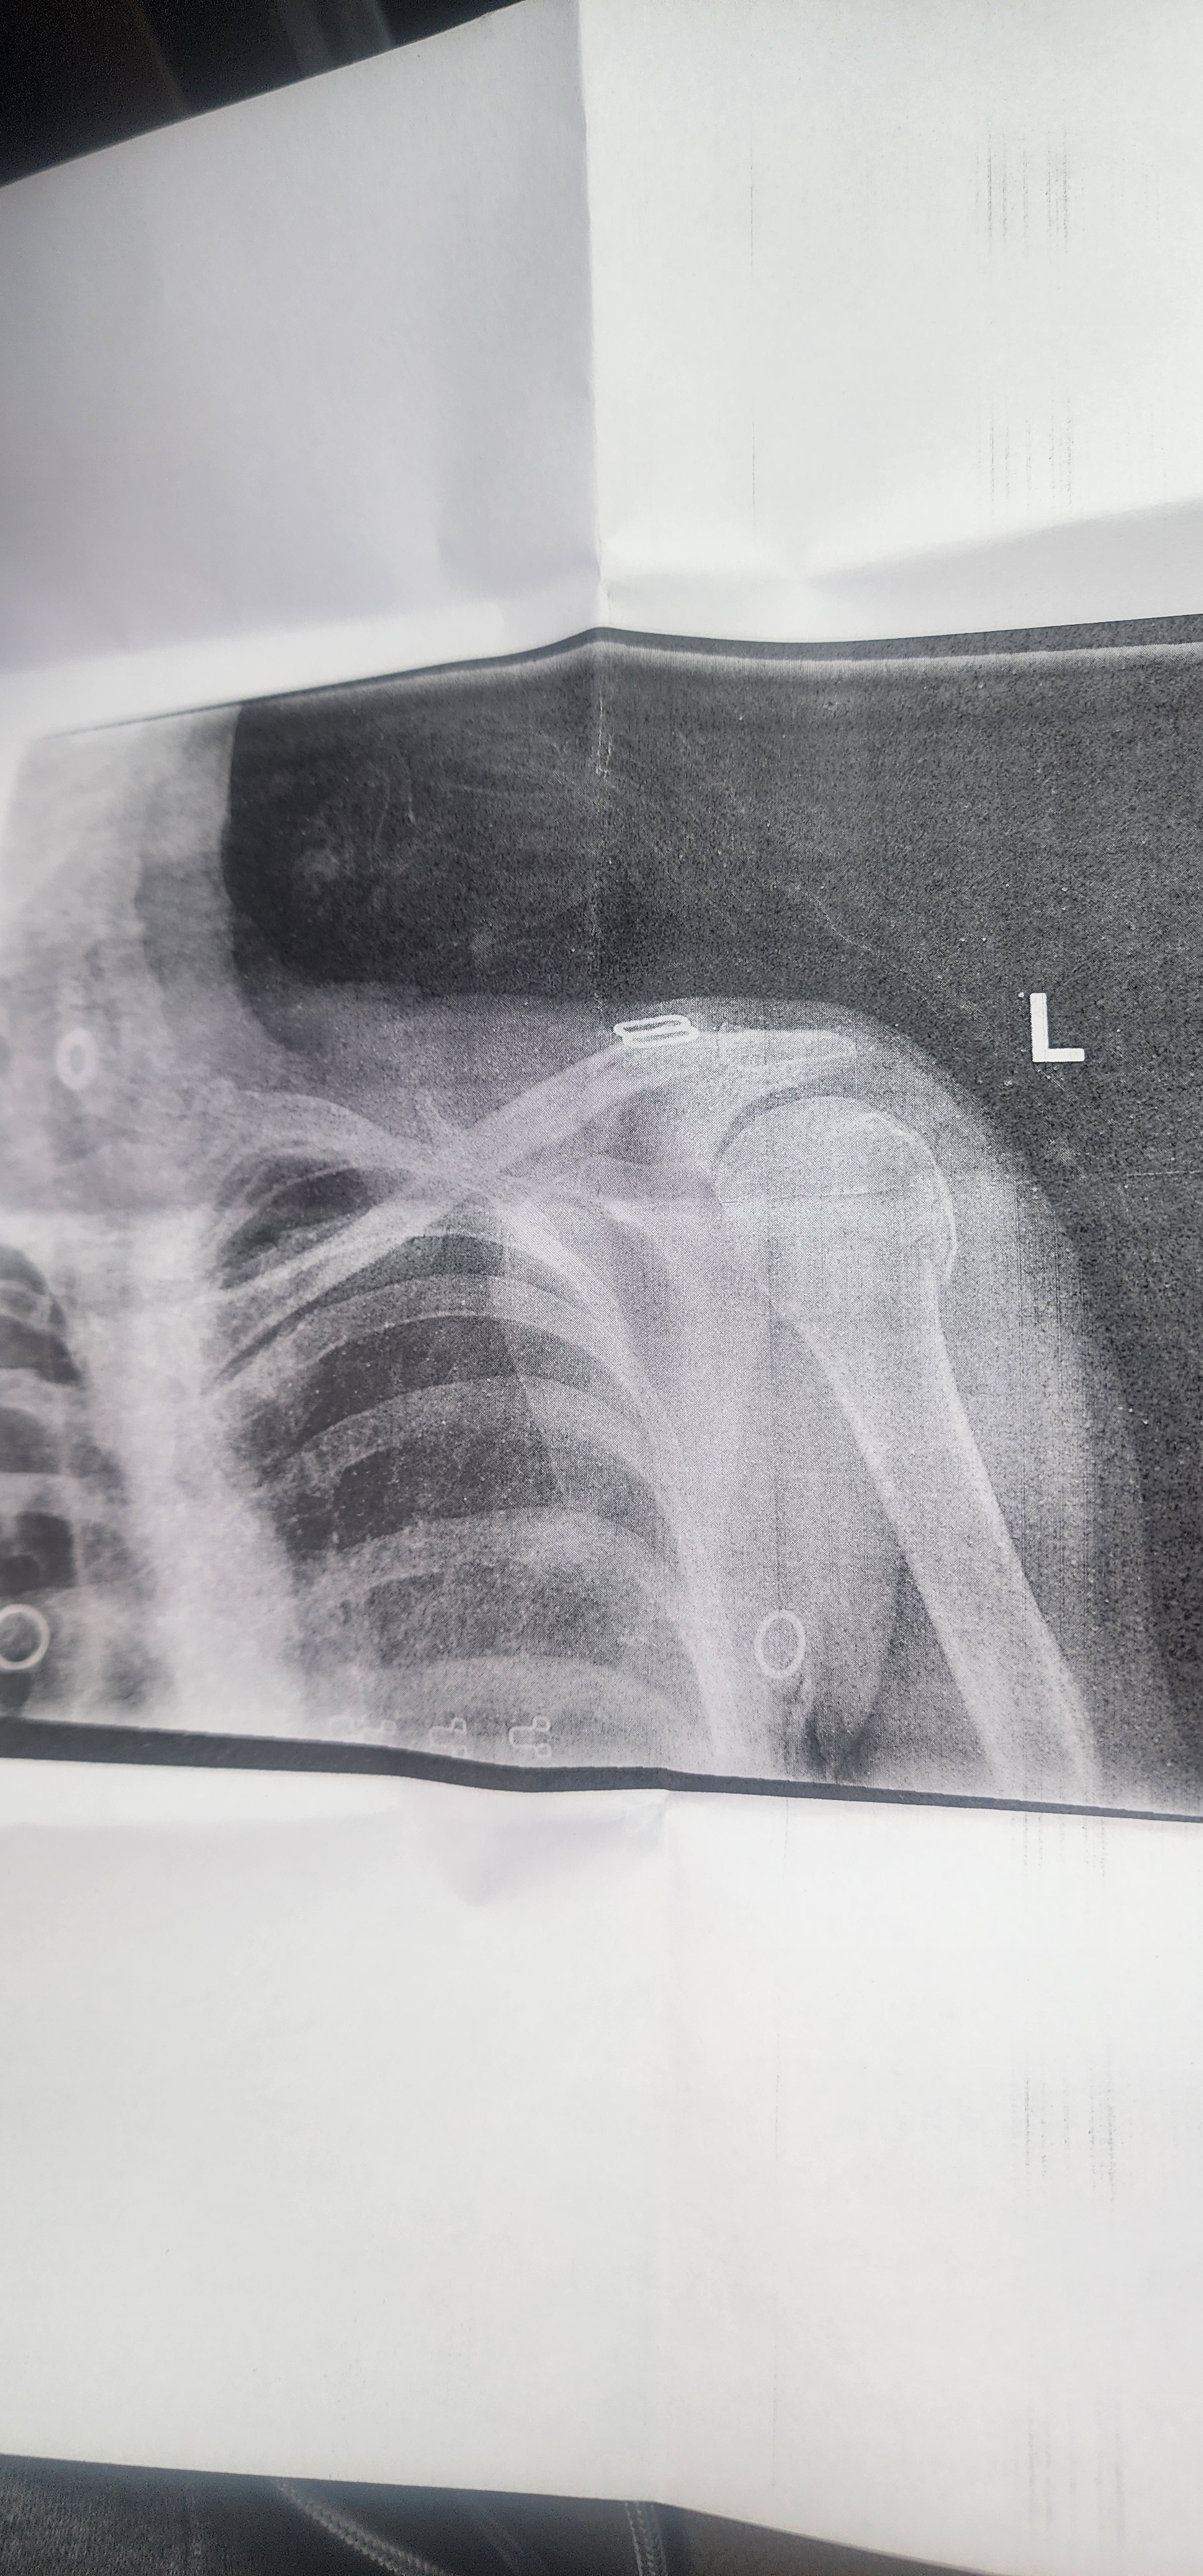

This morning, while delivering early morning packages for Amazon as an independent contractor, I slipped on ice due to a customer's unsalted driveway. I broke my humerus bone near my shoulder, and now I have no idea how long I will be out of work. With no income coming in, I am struggling to cover my bills, daily expenses, and my daughter's college tuition. The uncertainty of when I can return to work has made things even more overwhelming.